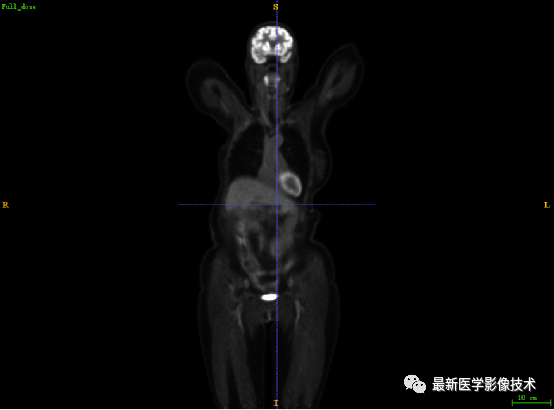

7.1、低剂量2重建结果

第一张是低剂量2的PET图像,第二张是full剂量PET图像,第三张是网络重建的PET图像。